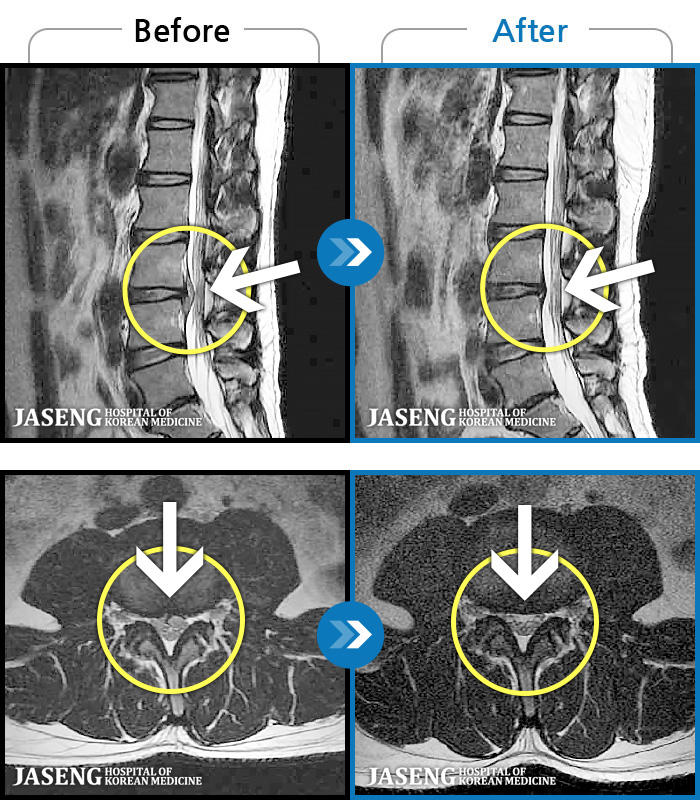

- MRI ġ

MRI ġ

1,237 MRI ũ ʸ Ȯϼ.

㸮 ϻ .